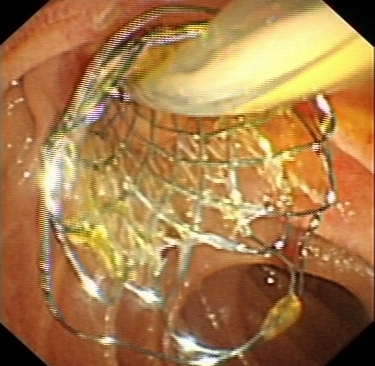

二、ERCP(內鏡逆行胰膽管造影術)

ERCP(內鏡逆行胰膽管造影術)是膽胰疾病精準內鏡診療技術,具有不開腹、風險小、創傷小、恢復快、住院時間大大縮短的優點,尤其是對年齡大、體弱多病的患者尤為適宜。ERCP主要運用于膽總管結石的取出,以及在經口膽道子鏡的輔助下完成肝內膽管結石的取出。

ERCP取出膽總管結石